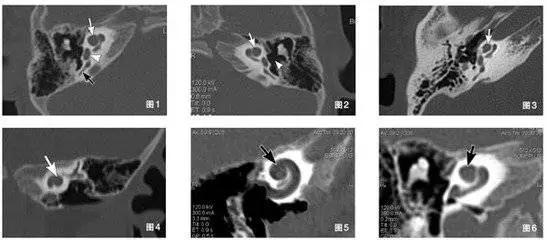

图1-6显示患者双侧耳蜗mondini畸形

对于术后的患者,多排螺旋CT可直观观察植入电极的形态及位置,准确评估电极在耳蜗内植入的数目,有重要的临床价值。

多排螺旋CT主要观察内耳结构(骨迷路结构)。耳蜗畸形中,除Michel畸形、耳蜗未发育为手术的绝对禁忌症,其他类型内耳畸形均非人工耳蜗植入的禁忌症。不同内耳畸形术后可能出现不同的并发症,多层螺旋CT及其后处理技术,能从不同角度、由二维到三维立体显示内耳结构的大体形态,对不同畸形做出细致的分类,能帮助临床医生更好地预测手术中可能遇到的问题,合理地选手术方式和判断预后,有很高的应用价值。